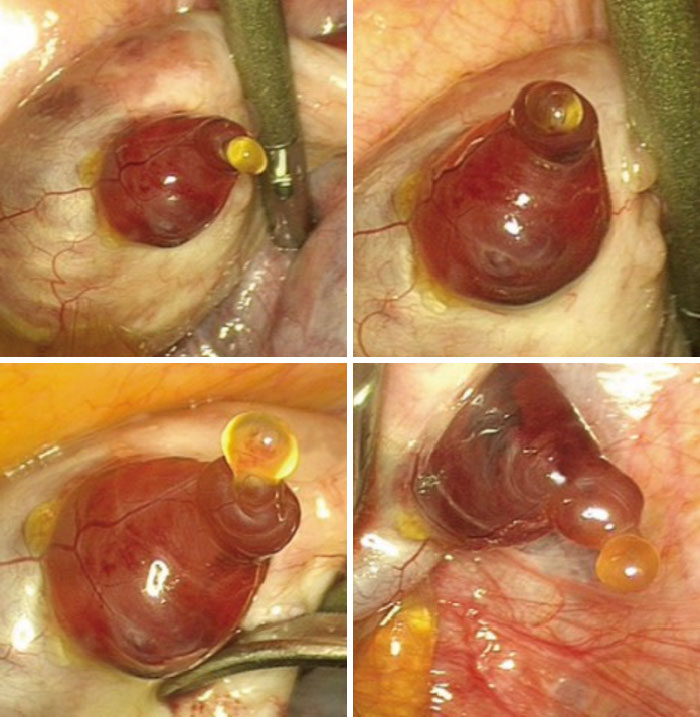

A Gynaecologist Captured A Human Egg Emerging From An Ovary While Performing A Hysterectomy

The image of rarely seen phenomenon of a human egg emerging from the ovary was captured by gynaecologist Jacques Donnez...